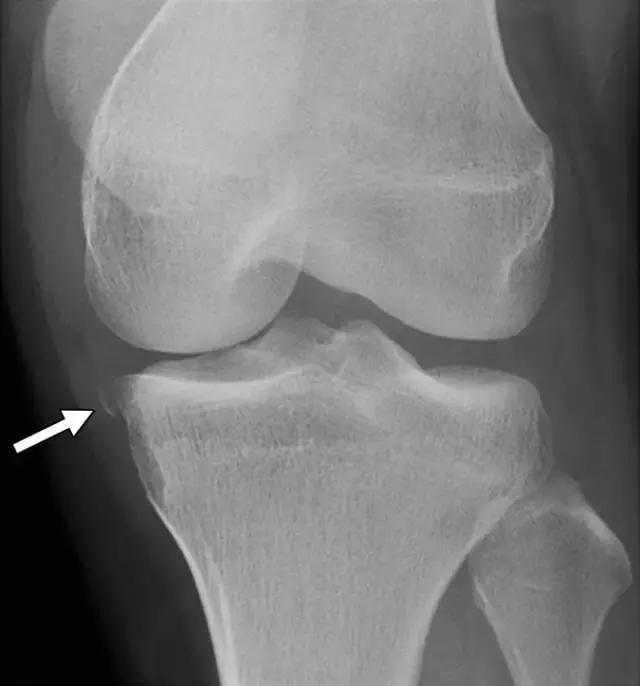

反向Segond骨折,是内侧胫骨平台的撕脱骨折,它是后交叉韧带严重受损的标志。这种骨折中的放射学检查结果与经典Segond骨折相似,只是反向骨折涉及胫骨近端的内侧(图6A)。据认为是由于内侧副韧带的深部荚膜组分的撕脱引起的(图6B),并且经常与内侧副韧带的严重损伤和相邻内侧半月板的周边损伤有关。

图6A -18岁的女性患有反Segond骨折。膝盖倾斜放射照片显示沿内侧胫骨平台的小撕裂性骨折(箭头)。